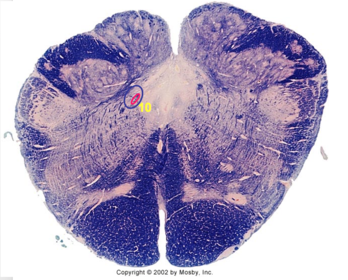

| Hypoglossal nucleus | |

| Hypoglossal nerve | |

| Dorsal motor nucleus of X | |

| Nucleus ambiguus | |

| Solitary tract | |

| Solitary nucleus | |

| ALS | |

| Medial lemniscus | |

| Medial longitudinal fasciculus | |

| Spinal tract of V | |

| Spinal nucleus of V | |

| Lateral (external, accessory) cuneate nucleus | |

| Medullary pyramids | |

| Anterior spinocerebellar tract | |